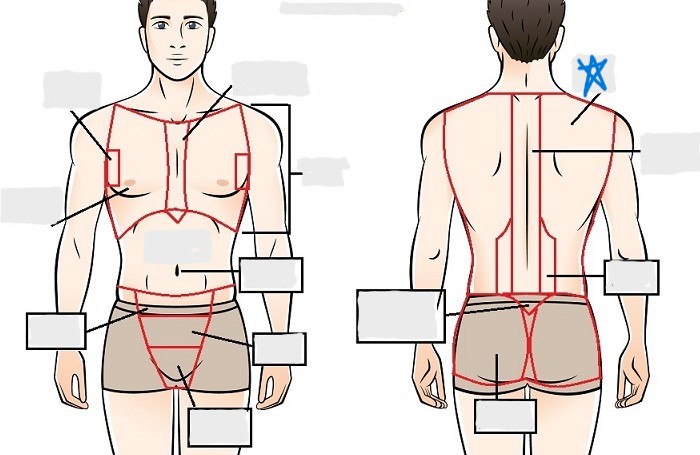

dorsal

scapular

vertebral

lumbar

sacral

gluteal

thoracic

sternal

mammary

axillary

abdominal

umbilical

pelvic

inguinal

pubic

perineal

appendicular

acromial

brachial

antecubital

olecranal

antebrachial

carpal

manus

coxal

femoral

patellar

popliteal

crural

sural

peroneal

calcaneal

plantar